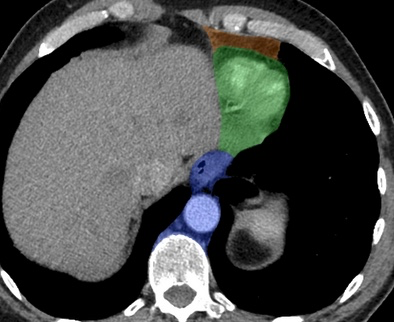

CT Annoté

médiastin mediastinal mediastinale médiastinal médiastinale